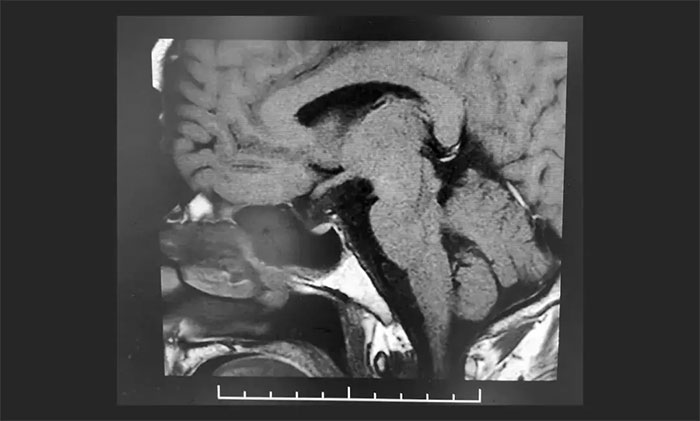

颅咽管瘤是位于鞍区或鞍旁区的生长缓慢的中枢神经系统良性肿瘤。起源于颅咽管的上皮细胞或 Rathke's囊的残留(造釉型)或由原始口凹残留的鳞状上皮细胞化生而来(乳头型)。颅咽管瘤可从垂体下丘脑轴的任何一点发生并沿此轴发展,肿瘤可从位于蝶鞍到大脑的第...[详细]